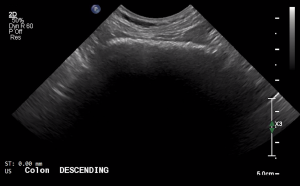

SIMON Ultrasound Database

This ultrasound database is a free resource for students and doctors!

Our collection includes videos of dogs, cats, horses, cows, humans, and many other species!